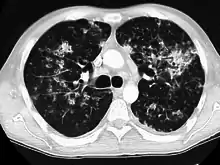

CT, 16 days after onset, showing extensive pulmonary parenchymal involvement consisting of irregular septal thickenings with ground-glass areas and centrilobular nodules with a peri-lymphatic distribution